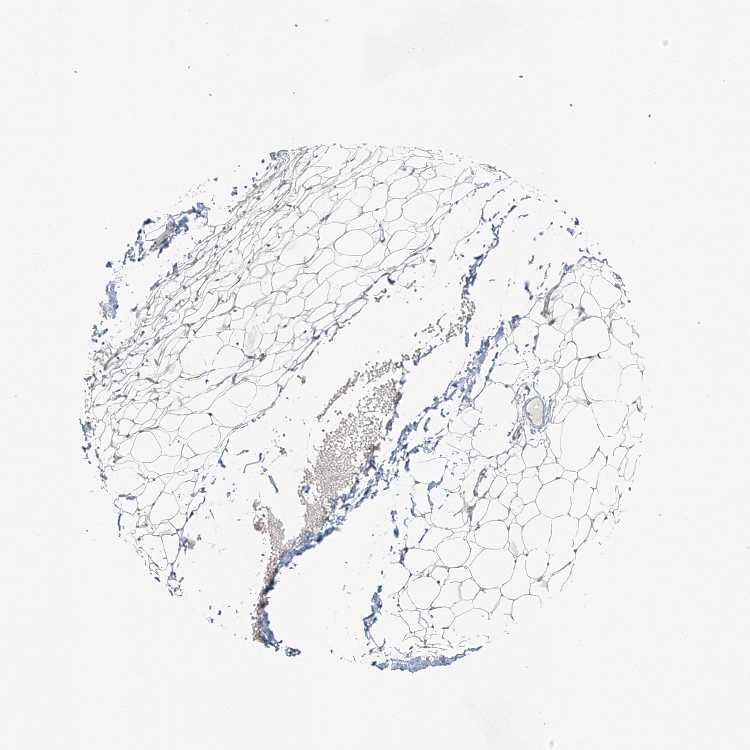

SOFT TISSUE 2 - Antibody stainingi

Antibody staining in the annotated cell types in the current human tissue is reported as not detected, low, medium, or high, based on conventional immunohistochemistry profiling in selected tissues. This score is based on the combination of the staining intensity and fraction of stained cells.

Each image is clickable and will lead to virtual microscopy that enables deeper exploration of all samples and also displays staining intensity scores, fraction scores and subcellular localization as well as patient and tissue information for each sample.

Antibody HPA034659

Fibroblasts Not detected

Peripheral nerve Not detected